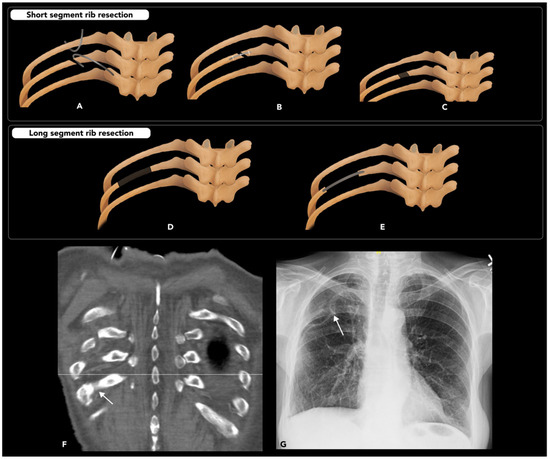

2.5.2. Rib Osteotomy